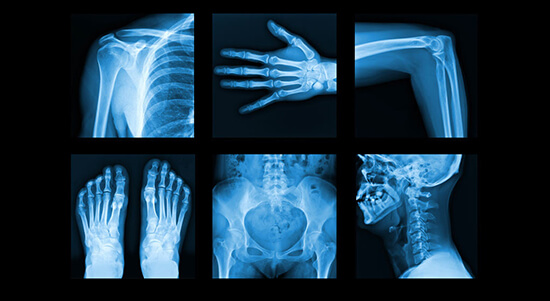

The Role of Radiographers in HealthcareRadiographers are often referred to as the “eyes of medicine.” Their expertise enables doctors to accurately diagnose conditions, monitor the effectiveness of treatments, and perform minimally invasive procedures. With their knowledge of imaging technology, they operate a range of equipment, including X-ray, MRI (Magnetic Resonance Imaging), CT (Computed Tomography) scans, and ultrasound. These images are crucial for identifying conditions such as fractures, cancers, infections, and cardiovascular diseases, helping guide the course of treatment.

Technological Advancements in RadiographyRadiography has come a long way since Roentgen’s discovery. Advances in digital imaging, such as 3D imaging and interventional radiology, have enhanced diagnostic accuracy while reducing radiation exposure. Techniques like MRI and ultrasound do not use ionising radiation, making them safer alternatives for certain cases. These developments mean radiographers must continually update their skills and knowledge, staying current with emerging technologies and maintaining a high standard of care.